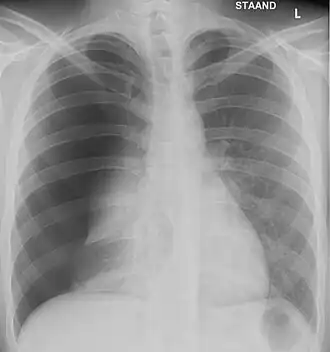

Wanneer de behandelende arts een pneumothorax vermoedt, kan dit vermoeden in eerste instantie bevestigd of ontkracht worden door een röntgenfoto van de borstkas (thoraxfoto, X-thorax). Dit is echter bij een spanningspneumothorax een vormfout. De diagnose kan hierbij gesteld worden op basis van klinische gegevens zoals het missen van ademgeruis bij de auscultatie (luisteren met stethoscoop). Hierop moet vervolgens meteen gehandeld worden, er kan niet gewacht worden op een foto.

Bij het bekijken van een röntgenfoto zoekt men naar de begrenzing van de ingeklapte long. Dit is een dun randje op de foto; dit is het longvlies. Tussen dit randje en de borstwand is er een holle ruimte, waarin er geen tekening meer is van bloedvaten of longweefsel. Dit is de pneumothorax. Dit is niet altijd duidelijk te zien; vooral bij een kleine, gedeeltelijke pneumothorax is de pneumothorax soms moeilijk vast te stellen. Mogelijk wordt er soms onderaan de longen vocht gezien: dit kan zowel bloed als pleuravocht zijn. Indien het mediastinum, de ruimte die tussen beide longen ligt, een beetje naar de gezonde kant is opgeschoven is dit een alarmteken voor een spanningspneumothorax. Soms ligt de middenrifspier ook lager dan normaal door de spanning in de pneumothorax.